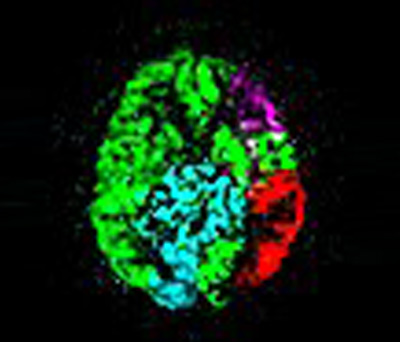

Методики бесконтрастной перфузии – Arterial Spin Labeling позволяют оценить общее (рис. 3А) и региональное кровоснабжения вещества моза (рис. 3Б) без болюсного введения контрастного вещества.

Рис. 3А. Бесконтрастная перфузия мозга. Методика 2d PCASL.

Рис. 3Б. Региональная перфузия мозга. Методика 2d STAR.